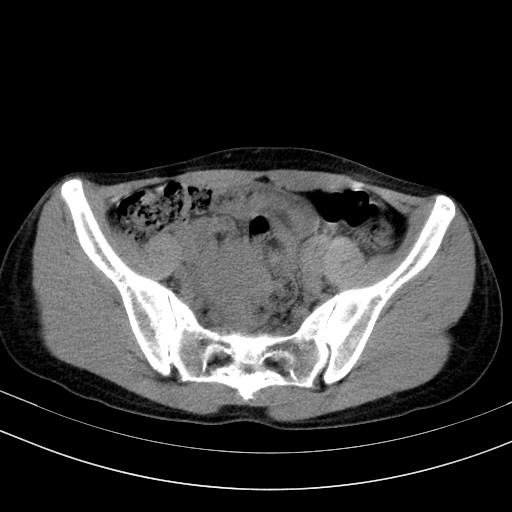

以下是引用随光逐影在2009-4-7 8:17:00的发言:[br]考虑宫颈占位性病变(宫颈癌?);建议行进一步检查。

以下是引用jiangjing在2009-4-7 16:46:00的发言:[br]宫颈增大,结构不清,右侧附件区可疑囊样占位,建议增强及mri 检查